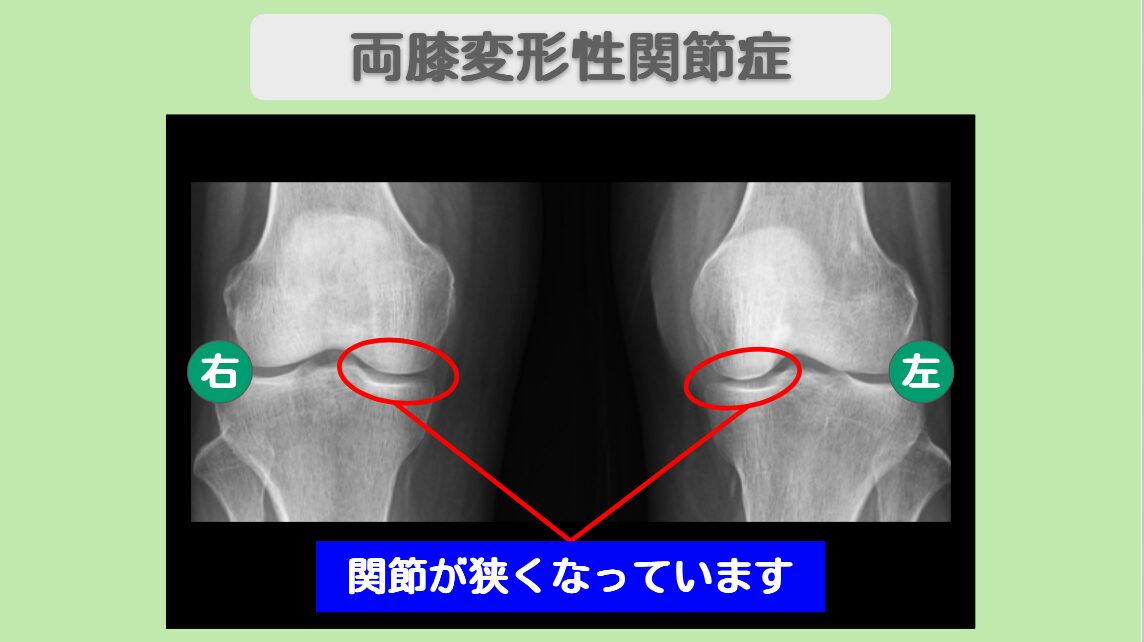

この患者様は、10年前からの両膝関節痛のため受診していただきました。当時、近くの整形外科で変形性膝関節症と診断されたそうです。以後、痛み止めを飲みながら過ごしてきましたが、最近では立っていることも辛くなってしまいました。レントゲンを再度撮影すると、軟骨のすり減りが進行しており、医師から人工関節を勧められました。まだまだアクティブな活動を続けたい患者様は人工関節を躊躇し、軟骨を再生させる方法を探され、幹細胞治療に辿り着いて当院を受診されました。

レントゲン所見